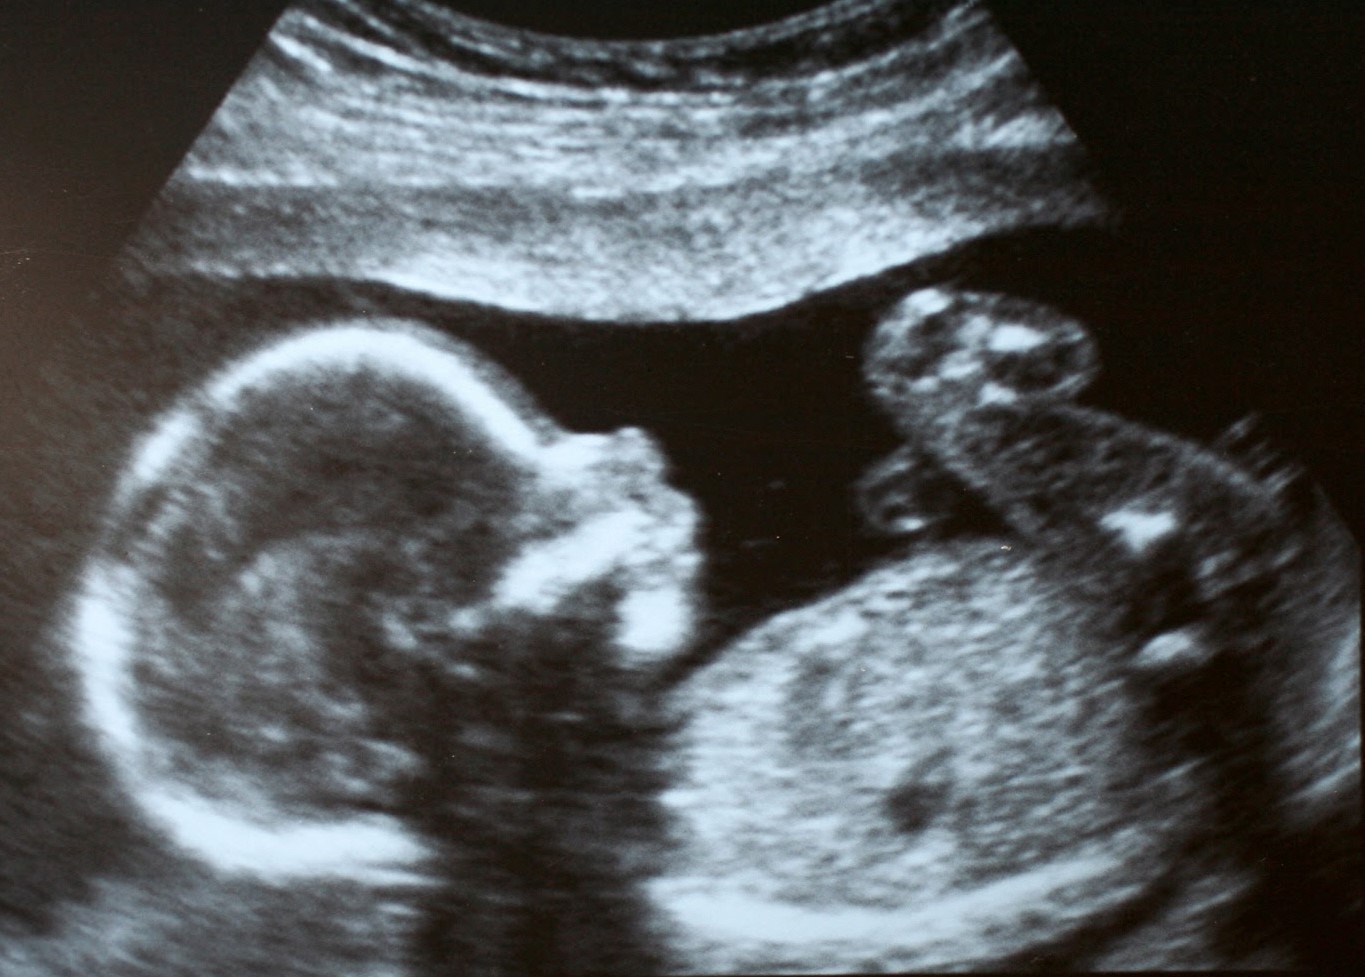

We all know women who delight in the changes their bodies are going through during pregnancy, are fascinated to see photos of the development of limb buds, fingers and toes, and are moved to see their children on the ultrasound screens, the hearts thumping away at 110 beats per minute. The child is a gift to them.

How is this connected with abortion? In our imaginations, the lower we go down the phylogenetic scale, the Great Chain of Being, the closer we get to the ontologically and morally ambiguous matter/nothing. (Think of how people dreaded the unseeable coronavirus, and death.) We associate evil with the unformed, the nothing, the mutable, monstrous blob, the small and insect-like. Some of us have pet mice, but who has pet beetles? I submit that many on the other side view the developing child not with scientific curiosity or wonder—no Psalm 139 for them—but as evil, and “nothing,” in its relatively unformed character. One young woman at a pregnancy medical center saw her developing unborn child on the ultrasound screen and F-bombed away with anger at top volume. (She went on to have her baby, happily, and deny that she ever really thought about abortion.)

There are about 2,700 pregnancy help organizations in the U.S., most of them run by Evangelical Protestants. Women get information, free pregnancy tests and ultrasounds, the facts on pregnancy and abortion, and practical and material help with becoming mothers. (Incidentally, it is quite common for women, when they see their children on the ultrasound screen, to say, “I had no idea.” They are surprised at how developed their children are, even at 6 weeks. About 80 percent choose life.) The counseling the women get informs their thinking about pregnancy and abortion with morality, obviously. They also are helped to imagine being mothers of these children. They give these centers the highest satisfaction ratings. They are deeply grateful for the help they received in having their children, rather than aborting them.